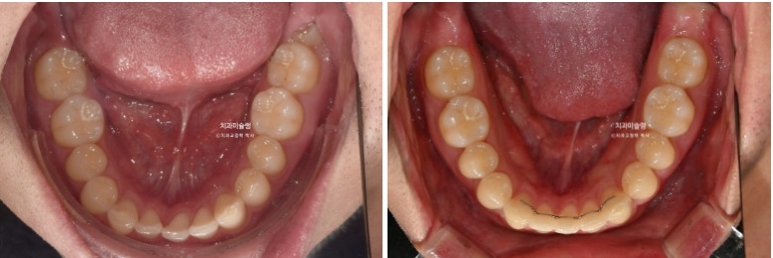

차례대로 교정 완료 직후 - 무삭제 라미네이트 부착 후 - 앞니 끝단 레진 치료 후 사진 입니다.

25년 11월 라미네이트 레진 등 보철을 포함한 모든 치료를 마무리 했습니다.

25.11

중심선은 잘 맞으며

어금니 교합도 좋습니다.